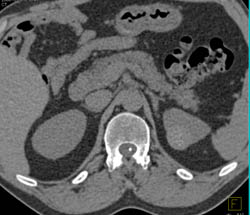

Angiomyolipoma of the Kidney